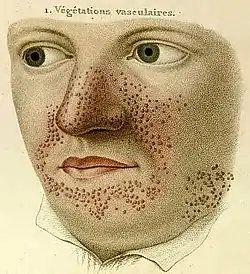

- 1835

- French dermatologist Pierre François Olive Rayer published an atlas of skin diseases. It contains 22 large coloured plates with 400 figures presented in a systematic order. On page 20, fig. 1 is a drawing that is regarded as the earliest description of tuberous sclerosis.[5] Entitled "végétations vasculaires", Rayer noted these were "small vascular, of papulous appearance, widespread growths distributed on the nose and around the mouth".[6] No mention was made of any medical condition associated with the skin disorder.